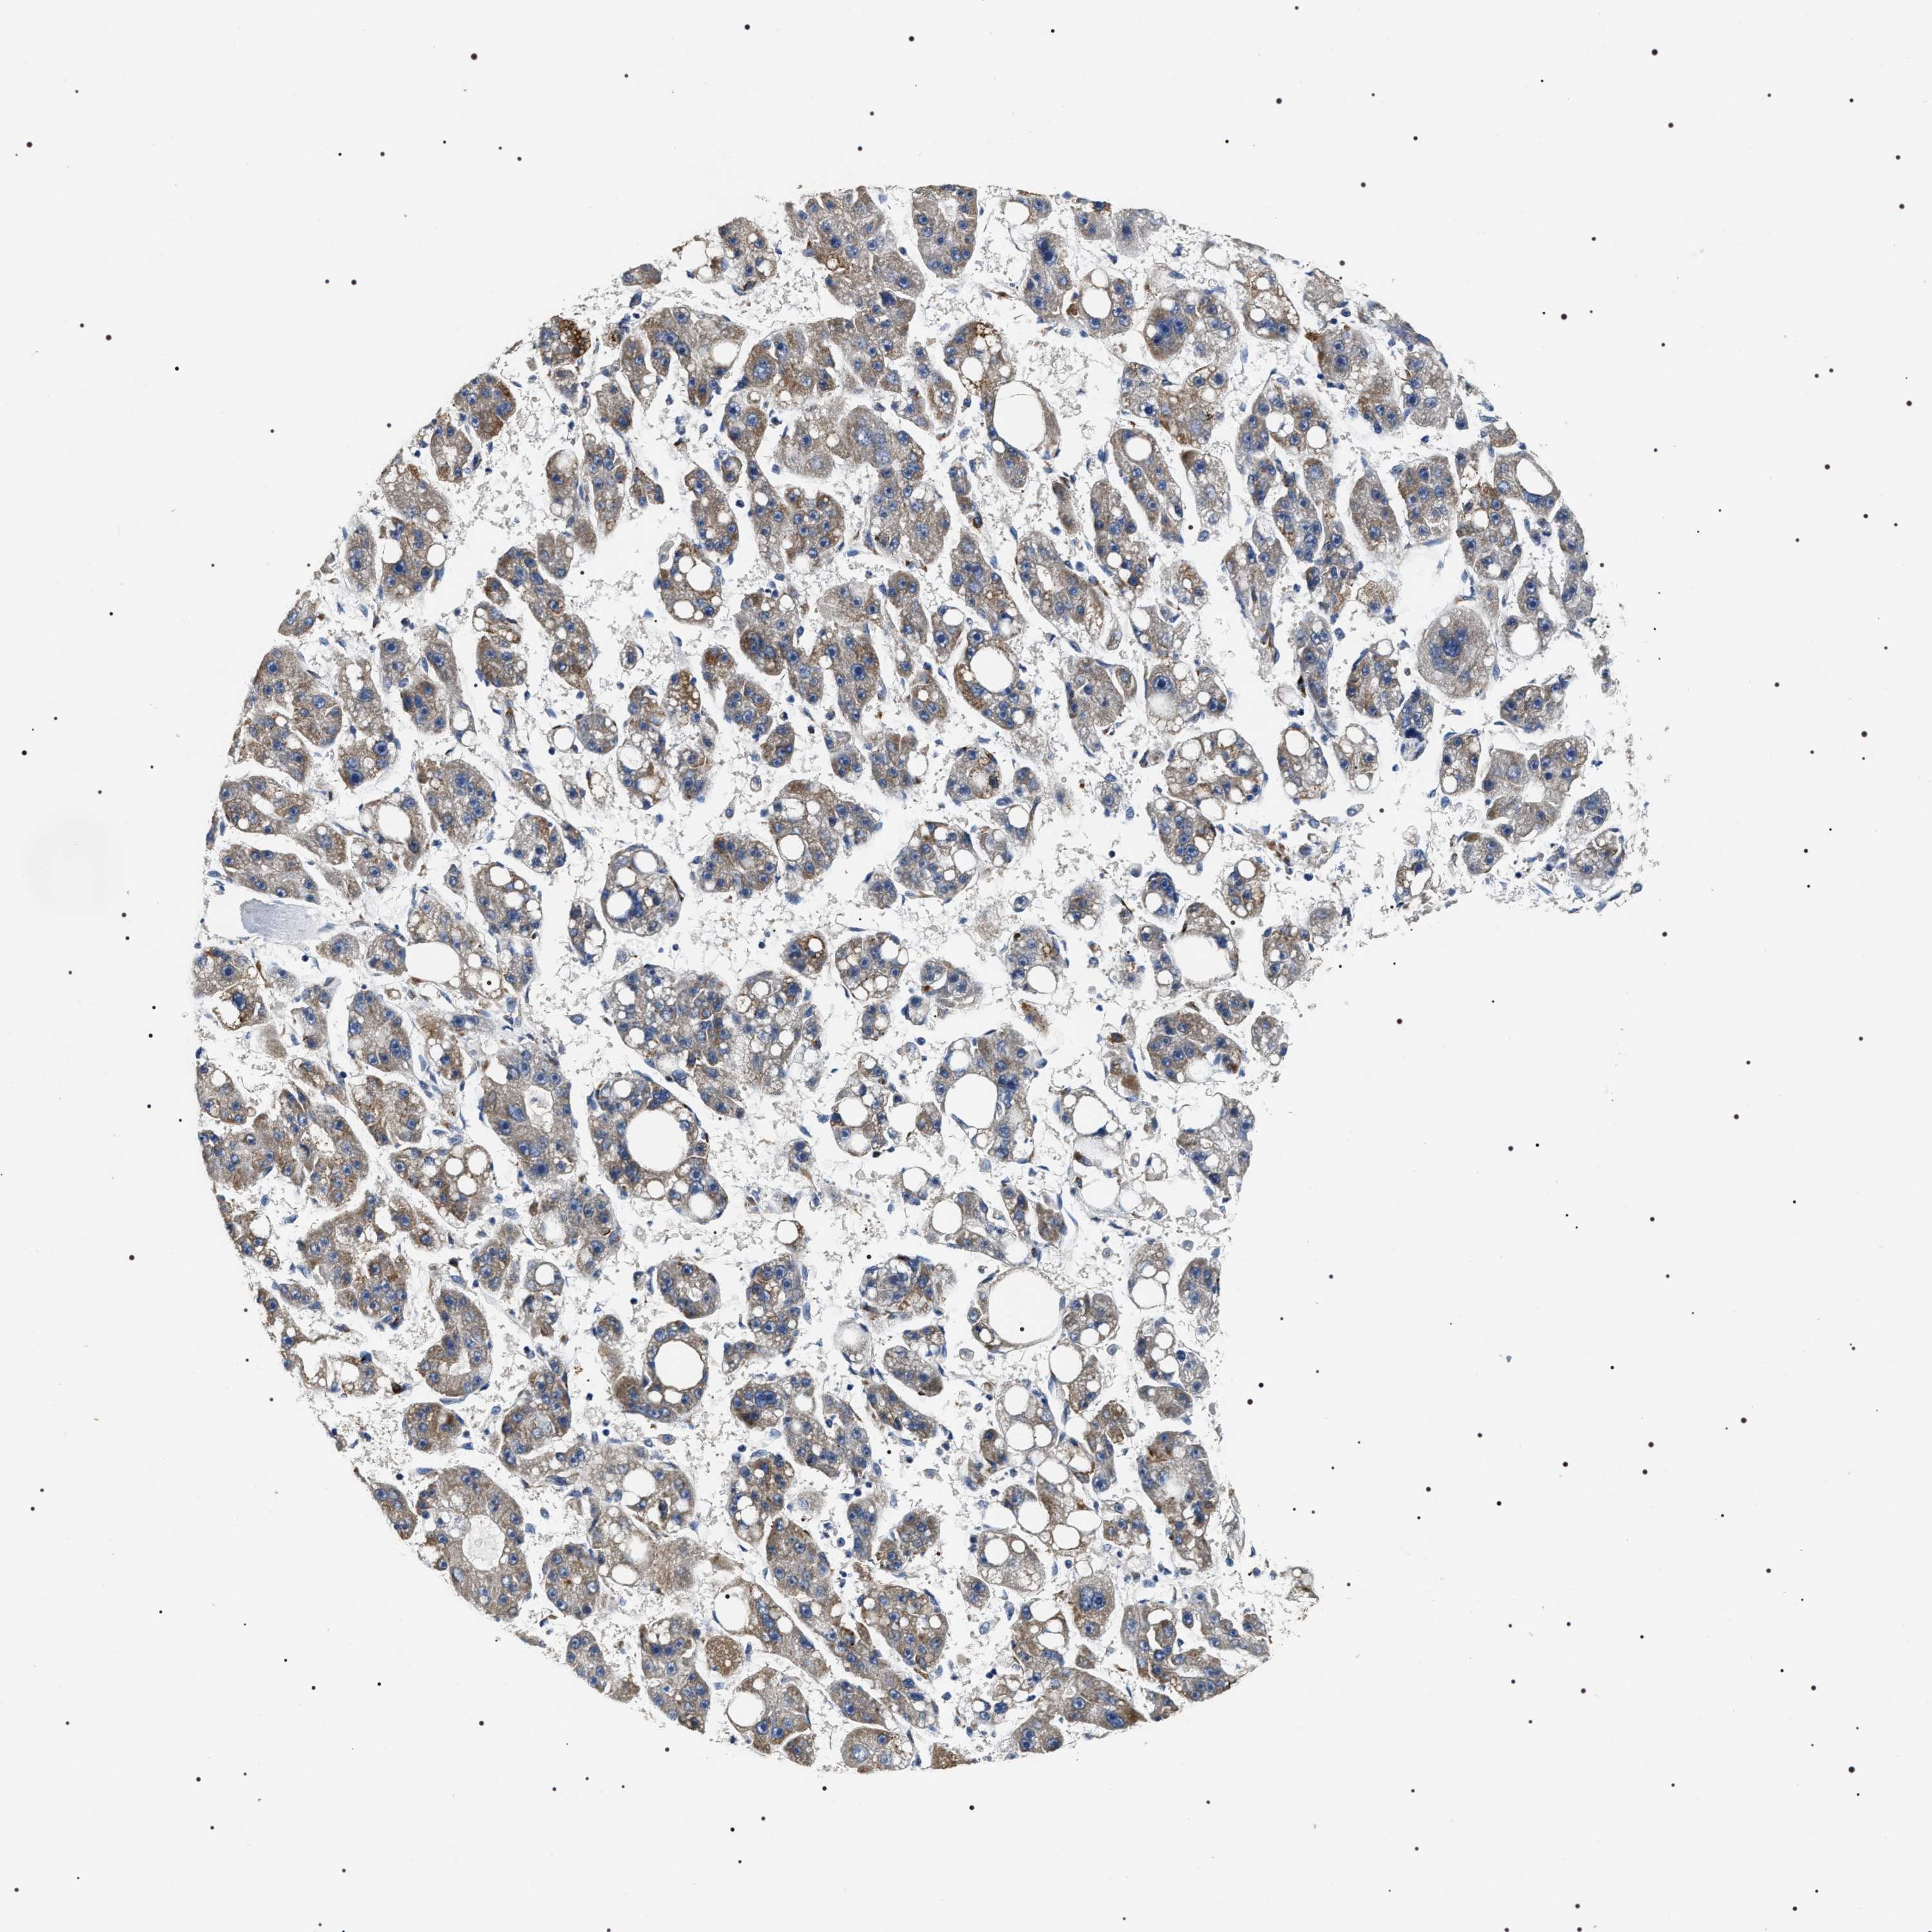

LIVER CANCER - Protein expressioni

A mouse-over function shows sample information and annotation data. Click on an image to view it in a full screen mode. Samples can be filtered based on level of antibody staining by selecting one or several of the following categories: high, medium, low and not detected. The assay and annotation is described here.

Note that samples used for immunohistochemistry by the Human Protein Atlas do not correspond to samples in the TCGA dataset.

Antibody stainingi

Antibody staining in the annotated cell types in the current human tissue is reported as not detected, low, medium, or high, based on conventional immunohistochemistry profiling in selected tissues. This score is based on the combination of the staining intensity and fraction of stained cells.

Each image is clickable and will lead to virtual microscopy that enables deeper exploration of all samples and also displays staining intensity scores, fraction scores and subcellular localization as well as patient and tissue information for each sample.

Antibody HPA020386

Staining

High

Medium

Low

Not detected

Intensity

Strong

Moderate

Weak

Negative

Quantity

>75%

75%-25%

<25%

None

Location

Nuclear

Cytoplasmic/membranous

Cytoplasmic/membranous,nuclear

Cholangiocarcinoma

Carcinoma, Hepatocellular, NOS